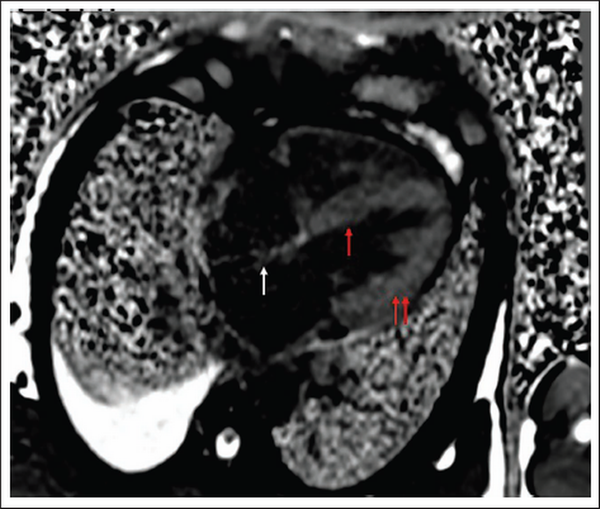

Visible Thickening of Interatrial Septum, Interventricular Septum, and Both Ventricular Walls on Cardiac MR.

Note: MR, magnetic resonance.

A clinical diagnosis of chronic congestive heart failure was made, and the patient was started on diuretics and investigated. Creatinine was 1.57 mg dl−1 with normal complete blood count and liver function tests (Table 1). Cardiac biomarkers revealed hs-tropI—383.7 ng l−1, Ck-MB—20 IU l−1, and NT-proBNP—8665 pg ml−1. Electrocardiogram (ECG) showed low voltage complexes in arm leads (Figure 1). Two-dimensional echocardiogram (2D ECHO) findings showed marked concentric left ventricular hypertrophy (LVH), LVEF—60%, abnormal global longitudinal strain pattern (apical sparing of longitudinal strain pattern), and cherry on top appearance. A low voltage ECG with concentric LVH and apical sparing of longitudinal strain pattern on 2D ECHO were suggestive of cardiac amyloidosis. A cardiac magnetic resonance (CMR) was done, which showed diffuse thickening of both ventricles, interatrial septum and interventricular septum, with reversal of the nulling pattern on T1 scout, with the diffuse enhancement of the walls of the thickened ventricles (Figures 2a,b and 3). A workup for primary amyloidosis was done. Serum immunofixation electrophoresis showed a monoclonal band in the beta region in the reference lane corresponding to lambda-only light chain, suggestive of light chain-only gammopathy (Figure 4). Free light-chain assay done showed involved FLC (lambda): uninvolved FLC (kappa) ratio was 14.01. iFLC was 835 mg l−1. dFLC was 775.39 mg dl−1. Serum B2 microglobulin was 5.39 mg l−1 (raised, cutoff—2.34 mg l−1). Total IgG was 14.06 mg l−1 (normal), IgA was 3.86 mg l−1 (normal), and IgM was 0.52 mg l−1 (normal). Flow cytometry immunophenotyping showed about 0.7% lambda-restricted abnormal plasma cells with reduced CD81 and aberrant CD28 expression. Bone marrow aspirate and biopsy were done, which showed trilineage hematopoiesis with myeloid preponderance and increased eosinophils and their precursors; plasma cells constitute about 5.5% of total nucleated cells with no evidence of amyloid deposit in the biopsy. A confirmatory diagnosis required a pericardial biopsy, but the patient refused for the same in view of the risk of adverse events. With cardiac ECHO/CMR findings and free light chain assay, a final diagnosis of AL-type cardiac amyloidosis, restrictive cardiomyopathy and heart failure with preserved ejection fraction (LVEF - 60%), on a background of chronic kidney disease, type 2 diabetes mellitus and hypertension was made. The patient was treated with intravenous Bortezomib (2 mg), Cyclophosphamide (300 mg) and Dexamethansone (40 mg). The patient showed clinical improvement and was discharged but was lost to follow-up.

Diagnosis of cardiac amyloidosis is often missed as it requires a high index of suspicion and low incidence overall. Laboratory tests, electrocardiography, cardiac imaging, and biopsy are required for making a diagnosis. Cardiac amyloidosis ECG pattern includes low voltage in limb leads (46%), due to electrically silent amyloid fibrils, and pseudo-infarct pattern (47%). Some ECGs may also depict arrhythmias, such as atrial fibrillation, AV blocks, and bundle branch blocks. Symmetric biventricular thickened wall with a spectrum of diastolic abnormalities (varying from abnormal relaxation to a restrictive filling pattern) is the hallmark of amyloidosis on 2D ECHO., , In cases where LV wall thickness is >12 mm without any history of hypertension, suspicion of cardiac amyloidosis should be kept high. Left ventricular ejection fraction is usually not affected till a later period in the disease course., As the longitudinal strain decreased on basal and mid-wall segments of the heart as compared to the apex, ECHO shows a pattern of apical sparing pattern, which is specific for cardiac amyloidosis. CMR is a better choice of investigation as it identifies the early stage of a diffuse subendocardial pattern of gadolinium enhancement and the late stage of transmural myocardial enhancement. These changes start to occur before the development of LVH., Mandatory investigations, in a patient with suspected amyloidosis, include serum and urinary protein electrophoresis and immunofixation to identify monoclonal protein., ,